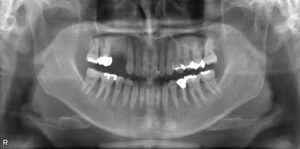

上顎臼歯3本欠損症例

BEFORE AFTER 72歳女性/上3本欠損/インプラント埋込手術 【治療内容】 左上の違和感と腫れが主訴でご来院さ…